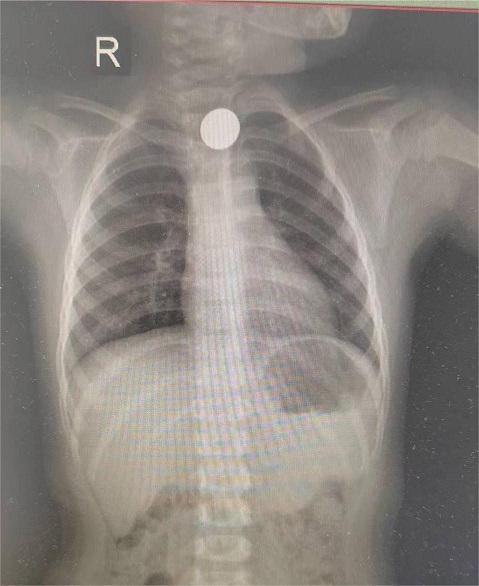

“医生……医生……快来看看我孩子!”3月31日上午,年纪两岁的淘淘(化名)妈妈焦急万分地抱着淘淘冲到榕江县人民医院向消化内科医生求助。原来,在家长不注意的时候,淘淘将一枚1元硬币放在嘴里把玩,一不小心将硬币误吞入口中。

经过主治医师杨文智仔细诊察,确认硬币已经滑入淘淘的食管内。由于孩子年龄尚小,食管壁相对薄弱,而硬币的直径明显大于食管的幽门口,取出过程中极有可能造成食管壁的损伤,甚至引发食管穿孔。硬币的光滑表面也增加了抓取的难度,这对内镜医生的技术提出了极高的要求。